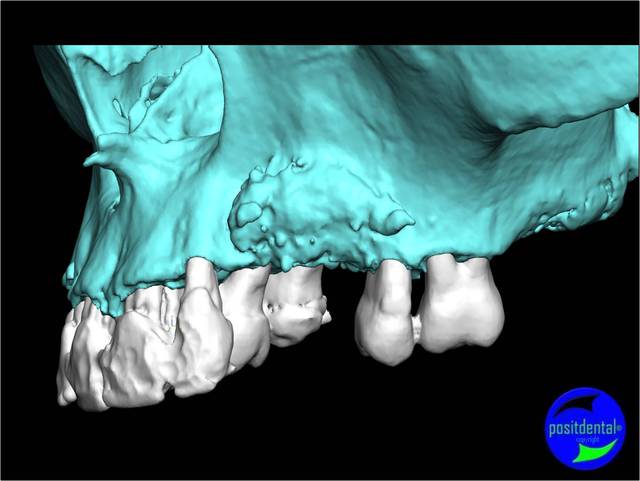

- la planification implantaire en 3D

Cas clinique n° 1

Positionner l'implant le mieux adapté, virtuellement, au meilleur endroit possible en tenant compte des contraintes anatomiques et de la future prothèse.